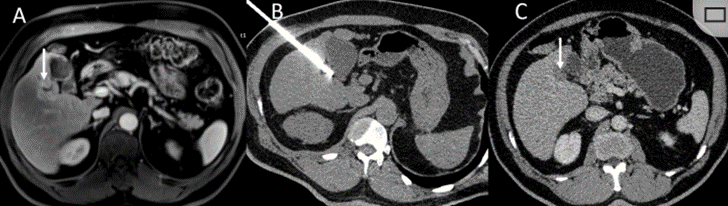

CT引导的冷冻消融

冷冻消融胆囊附近肿瘤病灶

(A)动脉期 MRI 显示胆囊附近有外周增强病变(箭头)。

(B)手术过程中 CT 显示冷冻探针位于病灶内。

(C)消融后,术后 1 个月CT 显示完全消融(箭头)。

冷冻消融肝包膜下肝细胞癌

(A)动脉期CT图像显示有一个包膜下结节(箭头)。

(B)门静脉期CT图像显示病灶区(箭头)。

(C) 在手术过程中的CT显示一个冷冻探针位于病灶内。

(D)消融后,术后1个月影像CT显示完全消融。